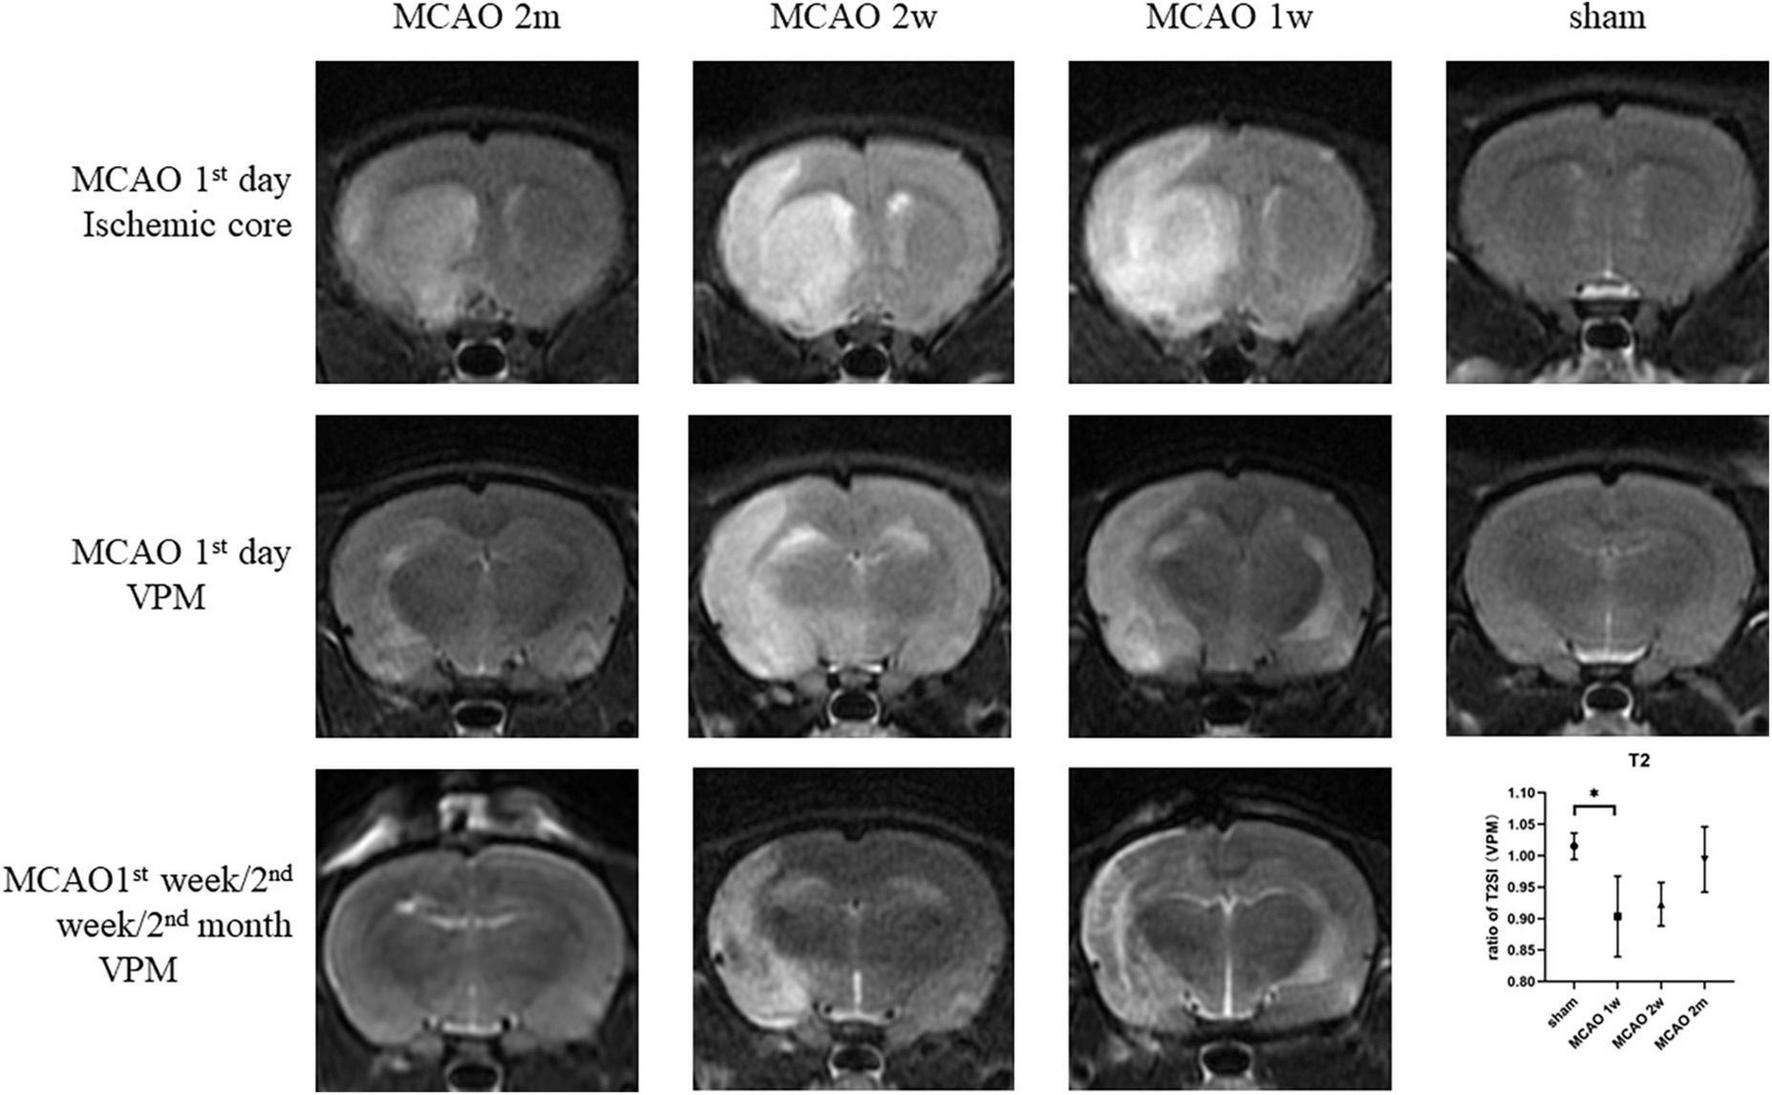

On the 1st day after MCAO, the ischemic cores were high signal at T2-weighted MRI for MCAO 2 month group, MCAO 2 week group, and MCAO 1 week group. The ratio of T2SI of the ipsilateral thalamus VPN touched its bottom at the 1st week after MCAO and gradually recovered at the 2nd week and the 2nd month (Figure 7).

FIGURE 7

The T2SI of the ischemic cores and the ipsilateral thalamus VPN. On the 1st day after MCAO, the ischemic lesions were high signal at T2-weighted MRI for MCAO 2 month group, MCAO 2 week group, and MCAO 1 week group. The ratio of T2SI of the ipsilateral thalamus VPN touched bottom at the 1st week after MCAO and gradually recovered at the 2nd week and the 2nd month. T2SI, T2 signal intensity; VPN, ventroposterior nucleus; MCAO, middle cerebral artery occlusion.